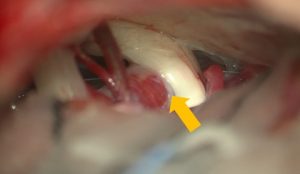

椎骨動脈による神経の圧迫